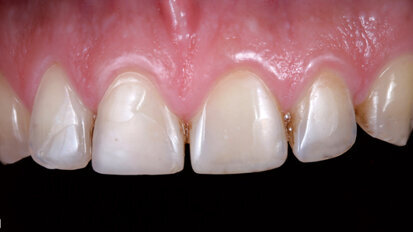

Between BOPT and BTA: A case report on shaping the gingival contour around tooth-supported restorations by means of provisional resin crowns

Shaping the soft-tissue contour around implants with provisional resin crowns after implant placement has become a frequently used technique in implant ...